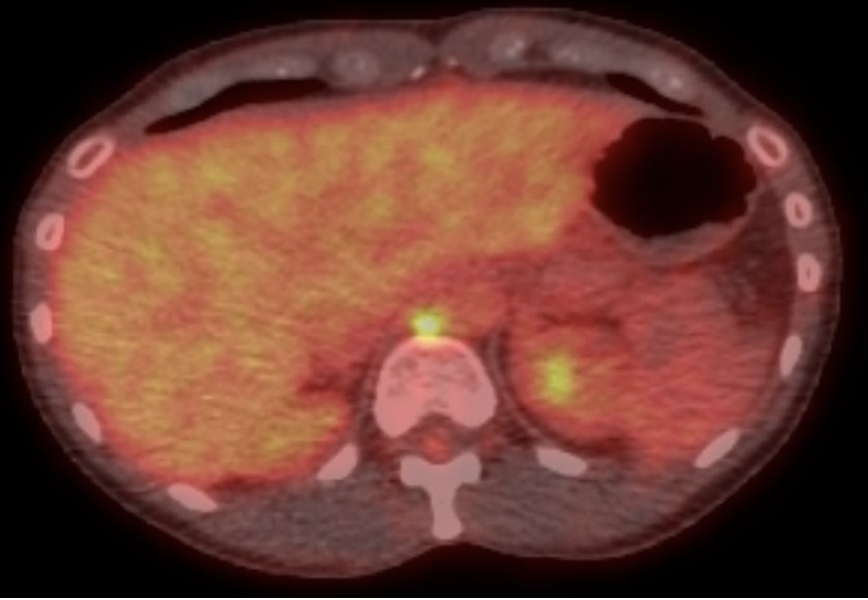

The patient was positioned prone oblique on the CT table (Figure 2). The procedure was performed under general anesthesia given the prone positioning, required precision for needle placement, and anticipated length of cryoablation. Under CT guidance, an 11-gauge bone access needle was advanced via a left transpedicular approach across the T12 vertebral body. Coaxial technique through this access was used to obtain both fine needle aspiration (FNA) and core biopsy samples (Figures 3-4). Immediate pathology assessment of the FNA samples confirmed metastatic adenocarcinoma. A single Endocare 17R cryoablation probe (Varian) was advanced through the 11-gauge access needle into the center of the nodal metastasis. Cryoablation was performed for 3 freeze-thaw cycles with intermittent CT monitoring to ensure adequate coverage of the lymph node and to minimize injury to the adjacent normal structures (Figures 5-6). All needles were removed, and the patient was extubated. After an uneventful overnight recovery, the patient was discharged home the following day.

This case example demonstrates an unusual application of a transosseous approach for biopsy and ablation. Follow-up PET/CT 6 months after cryoablation demonstrated no evidence of 18F-fluorodeoxyglucose (FDG)-avid disease (Figure 7).

FIGURE 7. Follow-up FDG PET/CT fused and attenuation correction CT axial images demonstrated no residual FDG activity at the site of treated metastasis. Linear sclerosis is noted along the bone needle trajectory, consistent with osseous healing.